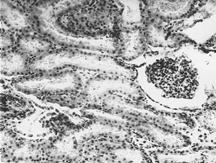

Рисунок 6. Почки. Группа № 2

Зернистая дистрофия основной массы эпителия извитых канальцев (Увел. 400).